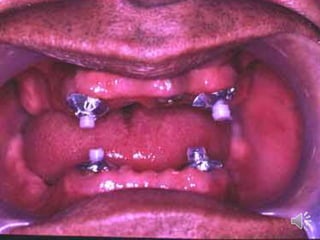

ABUTMENT WITH ATTACHMENTS

Attachments are small precision devices.

Objective is to improve retention of denture base.

Most attachments are secured to abutment by a cast coping.

Consists of two parts o Male o Female